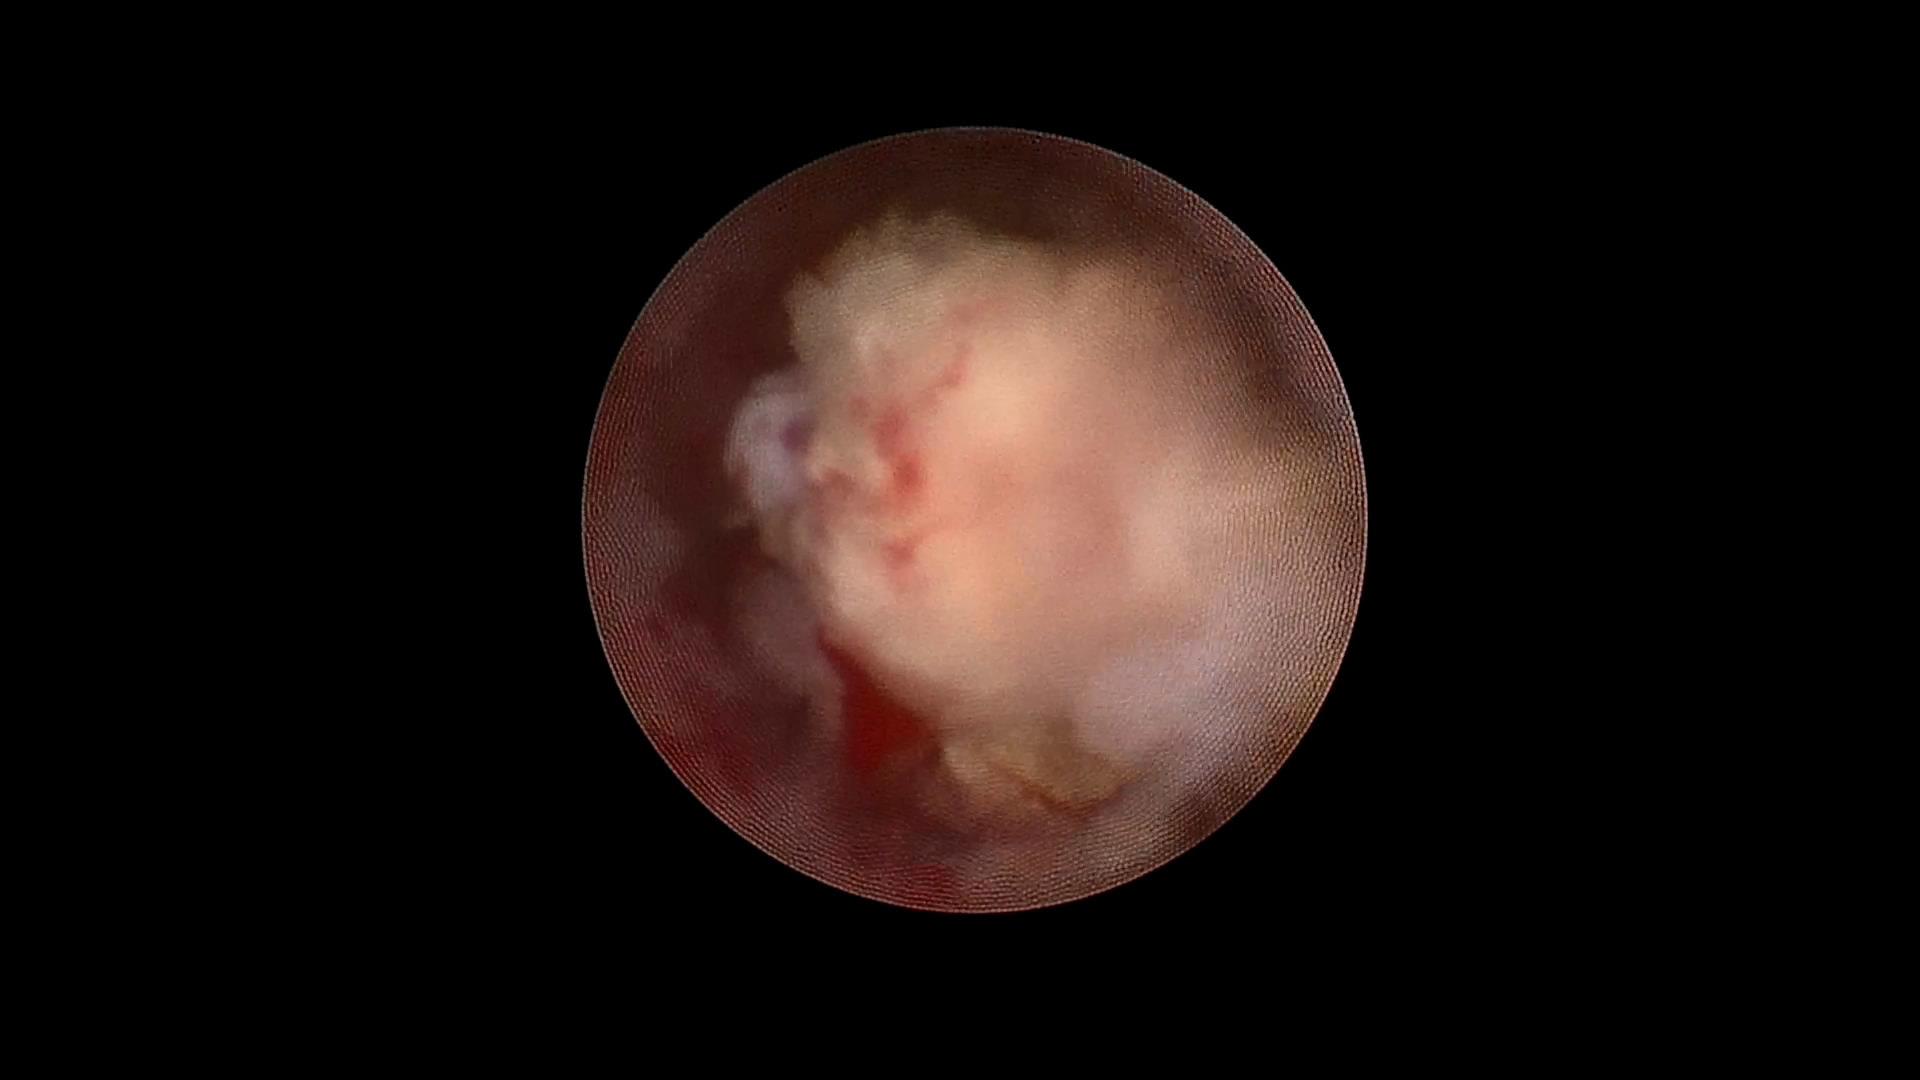

术中见左肾如皮囊样扩张,正常的肾实质已消失

皮囊肾体积巨大,切开菲薄皮质并吸出积水,增加手术操作空间